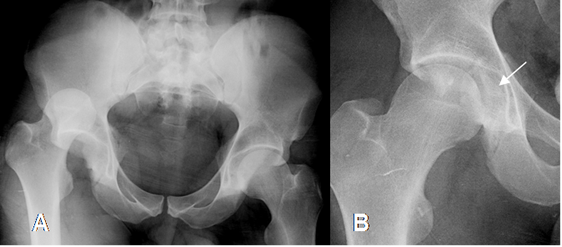

Fig 65. Luxación posterior de cadera.

A: Rx AP. Luxación posterior, con desplazamiento superior de la cabeza femoral derecha.

B: Rx AP. Luego de la reducción, se aprecia fractura del acetábulo con fragmento óseo medial, que impide la completa reducción.